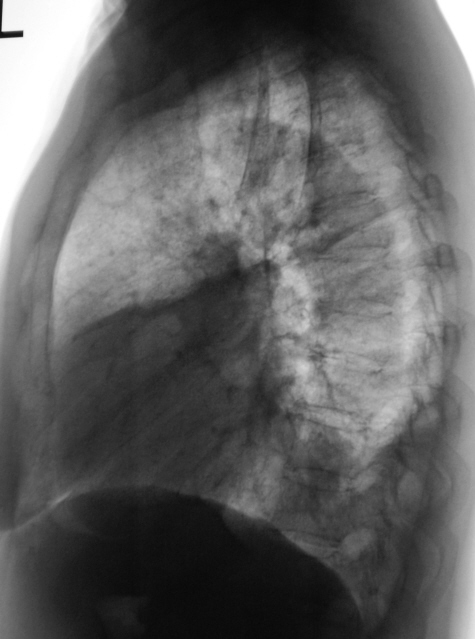

Томограмма в прямой проекции.

Валентин Львович. Я бы подумал об ателектазе нижней доли левого легкого. Викарная эмфизема верхней доли левого легкого. Рекомендация: бронхоскопия, КТ.

Мои шесть копеек. Заключение: Пневмония в нижней доле левого легкого с сопутствующим плевральным компонентом в стадии обратного развития. Организация выпота в нижней части левой плевральной полости.

Что картина без динамики - не согласен, налицо уменьшение объема и интенсовности затемнения, контуры компонентов стали более четкми.. Поперечник сердечной тень, конечно расширен, но для ТЭЛА характерна митрализация конфигурации (индекс Мура, и все такое).

ИМХО слева осумкование выпота (для организации срок мал). Имеется также расширение верхней 1/3 средостения переднего и среднего, больше вправо, туда же смещена трахея. Целостная картина не складывается... Наверное не обойтись без КТ.

ИМХО слева всё же осумкование выпота, а малый объём перетекающей жидкости не может так сместить трахею, кроме того, смещение её видно и стоя! И наконец, на последней томограмме – если только это не ошибка метода – видим довольно крутой дугообразный изгиб трахеи, как раз напротив как бы выпота. Предполагаю нечто экспансивно растущее в верхней 1/3 средостения. И тут уж не обойтись без КТ.

Петрович! Вы пишете: "Предполагаю нечто экспансивно растущее в верхней 1/3 средостения". Да об этом думалось и думалось интенсивно. С этой целью дополнительно и представлен увеличенный фрагмент томограммы, выполненной в прямой проекции и именно верхней ее части.